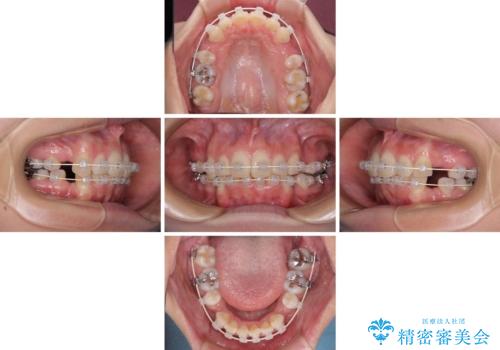

デコボコで飛び出した前歯 ワイヤー装置による抜歯矯正

- 審美装置

- 2年2ヶ月

- 上下前歯のデコボコと、飛び出した前歯を気にして来院された患者様です。

口元を積極的に引っ込めるために、上下左右の小臼歯計4本を抜歯することとしました。

咬み合わせが深く、咬合力強いため、補助装置を使用しながら積極的に口元を下げることとしました。

矯正治療前の咬み合わせで、前歯がすり減ってしまい、歯列が整ったときに先端がガタガタになってしまったため、矯正治療後に形態修正を行いました。